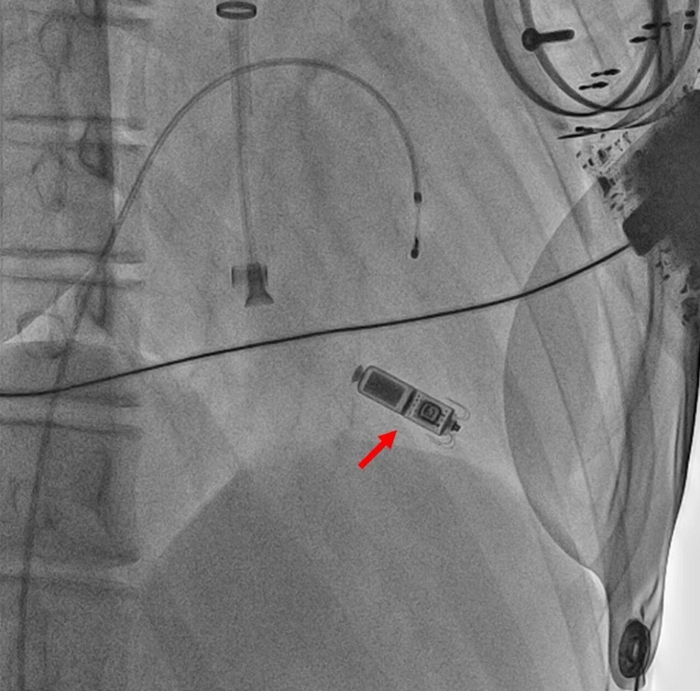

日前,首都医科大学附属北京天坛医院心脏及大血管病中心为一名罕见线粒体脑肌病合并心脏 Ⅲ 度房室传导阻滞的成人患者成功植入无导线起搏器,据悉,这也是国内首例此类成人患者接受无线起搏器植入的成功案例,填补了成人线粒体脑肌病无导线起搏器植入的空白。

由于目前国际上尚无成人线粒体脑肌病患者植入无导线起搏器的相关病例报道,闫朝武团队并无成熟经验可供借鉴,针对手术中可能出现的各类问题,团队制定了详细的应急预案。但让大家没想到的是,从手术一开始,挑战就接踵而至。“患者刚刚进入手术室,就突发心脏骤停,我们马上开展紧急抢救。”闫朝武介绍,手术团队为患者植入了临时起搏器,迅速稳定他的心率和血压,为后续手术奠定基础。在手术中,当团队尝试经过颈静脉植入无导线起搏器时,因为患者心肌病变严重,起搏器植入位点的选择又成了难题。经过3个多小时的精细操作,手术团队两次精准更换起搏器植入位点,最终成功完成植入。术后患者起搏心率稳定在50 次 / 分,血压恢复至 100/70 mmHg,乏力、头晕、黑矇等临床症状得到明显改善,生命体征趋于平稳,手术效果显著。